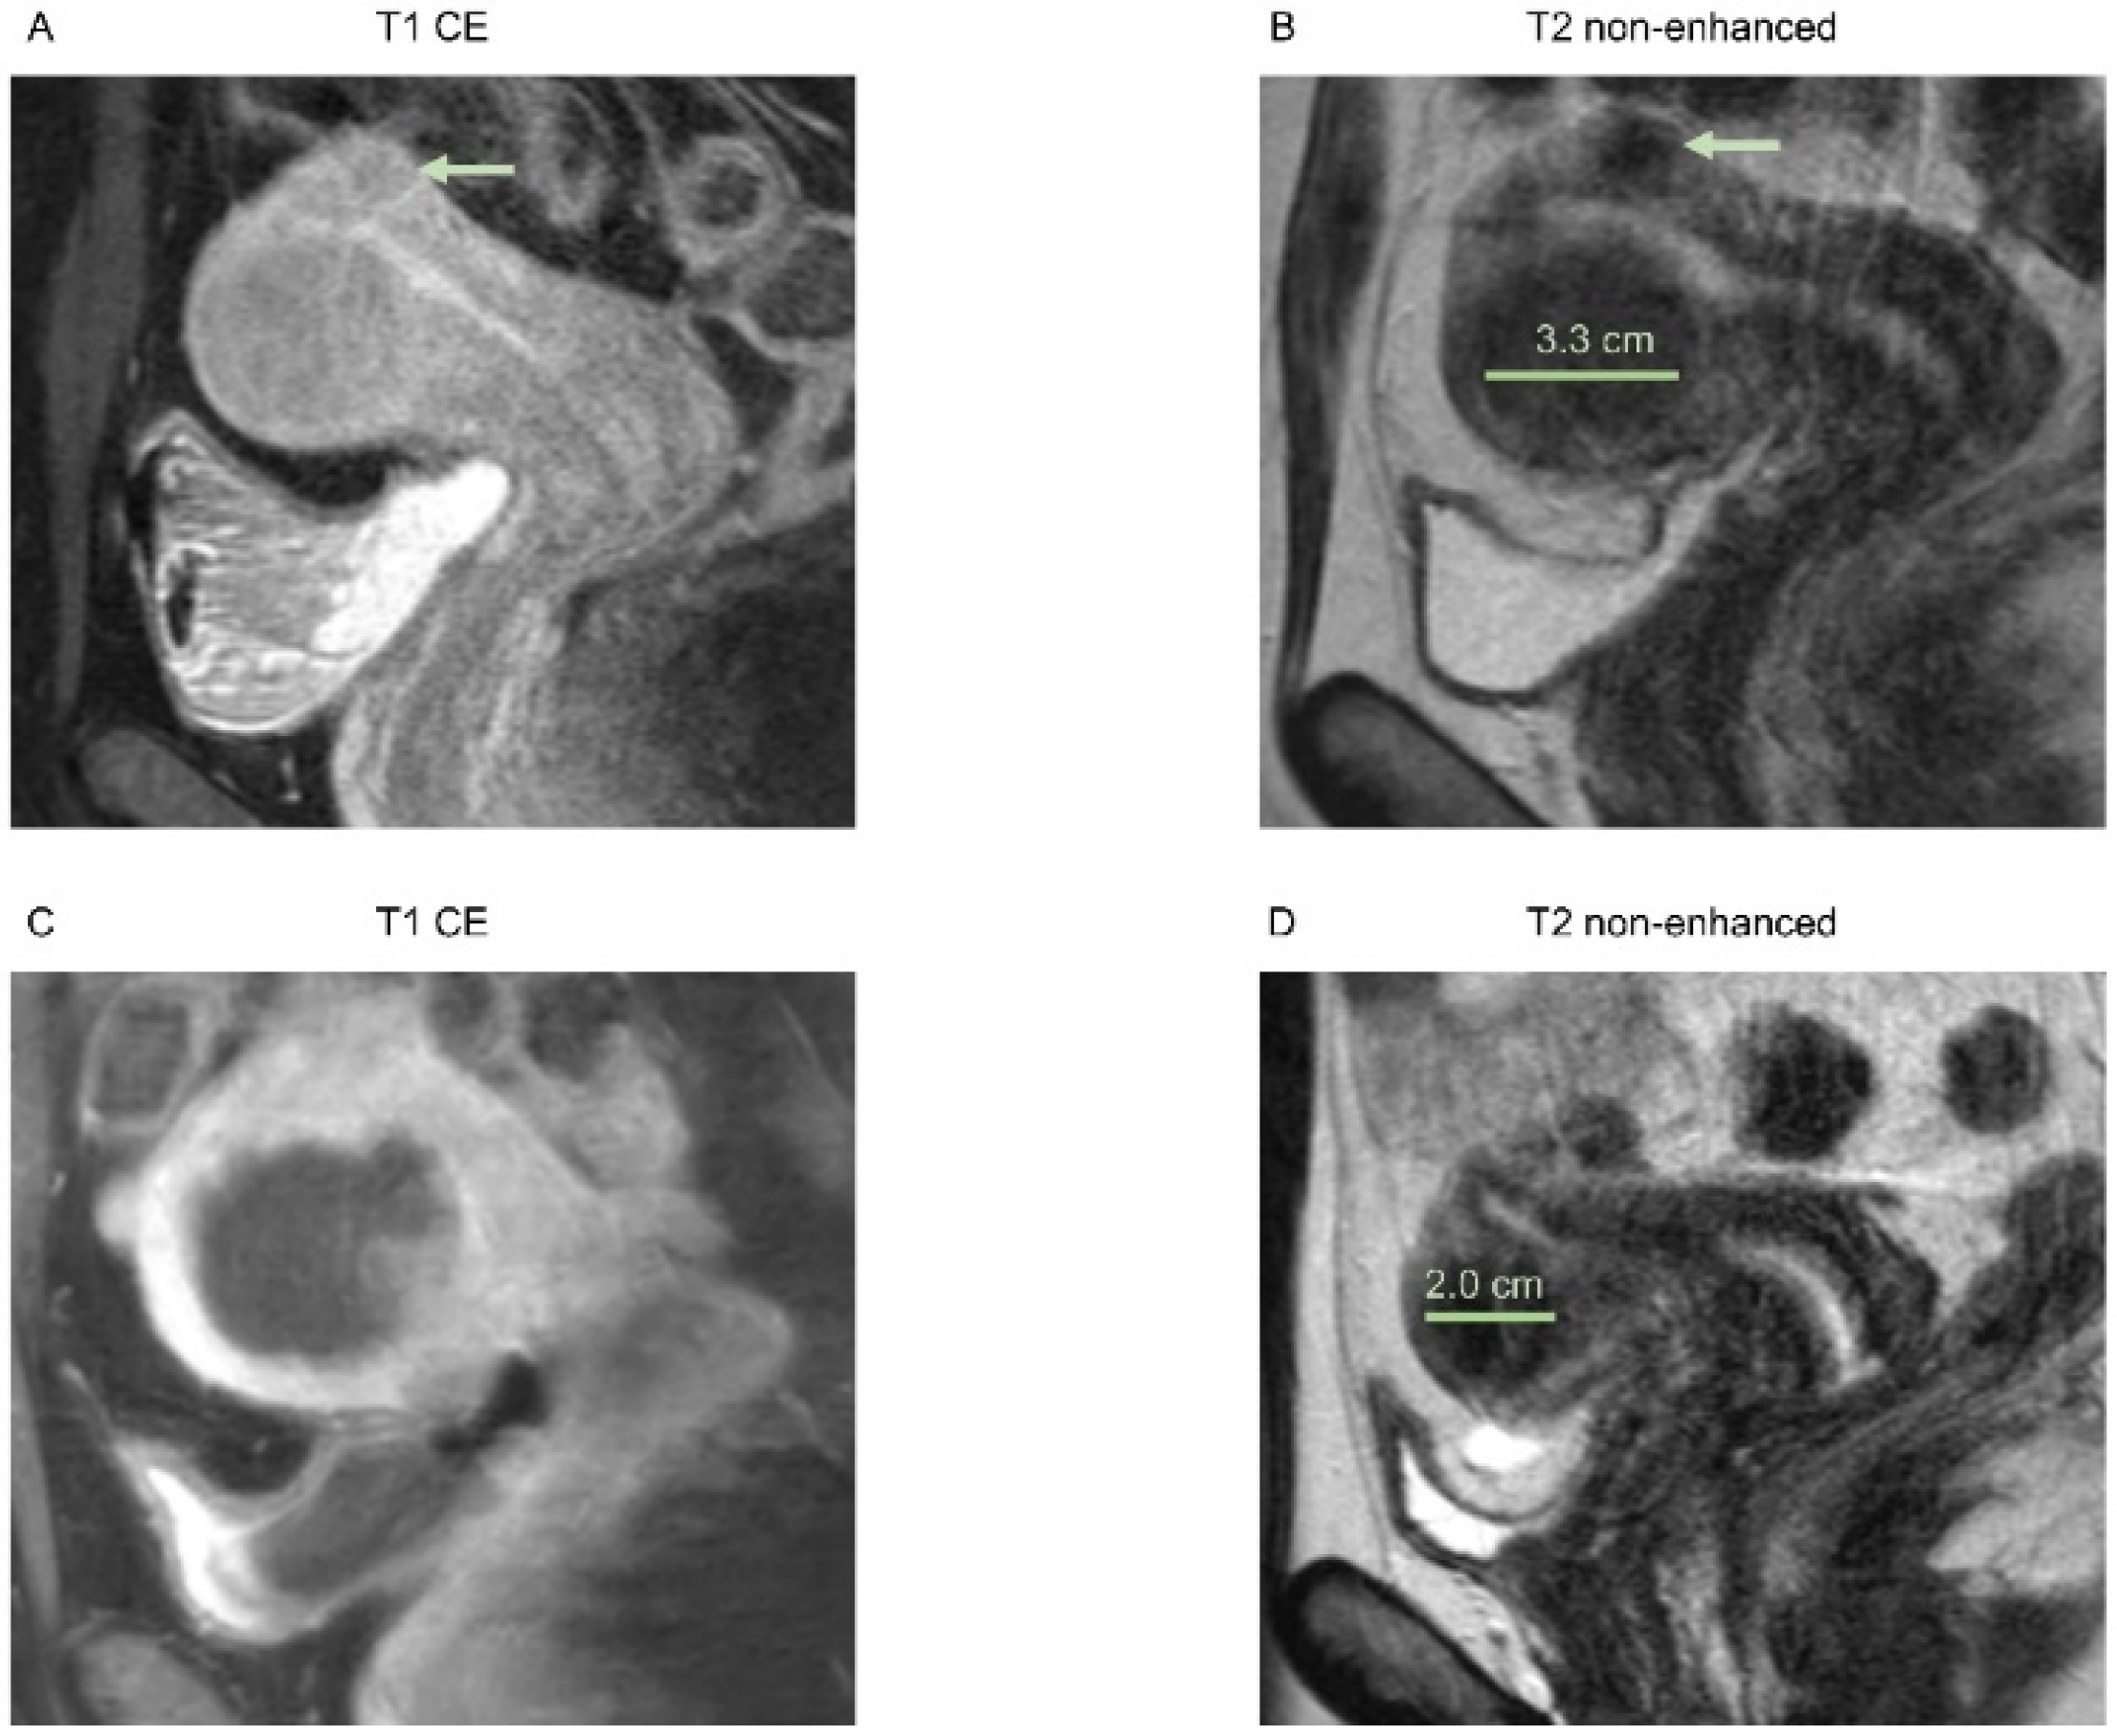

3.2. Morphological Assessment